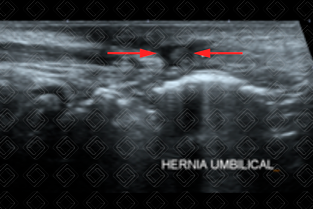

Texto alternativo para a imagem Figura 1. Créditos: Dra. Elazir Mota - Rio de Janeiro/RJ

Descrição das figuras 1 e 2: Ultrassonografia de parede abdominal evidenciando diástase dos músculos retoabdominais com herniação de conteúdo adiposo (setas vermelhas). Estudo é realizado de forma dinâmica, ou seja, em repouso e durante a realização de manobra de Valsalva.